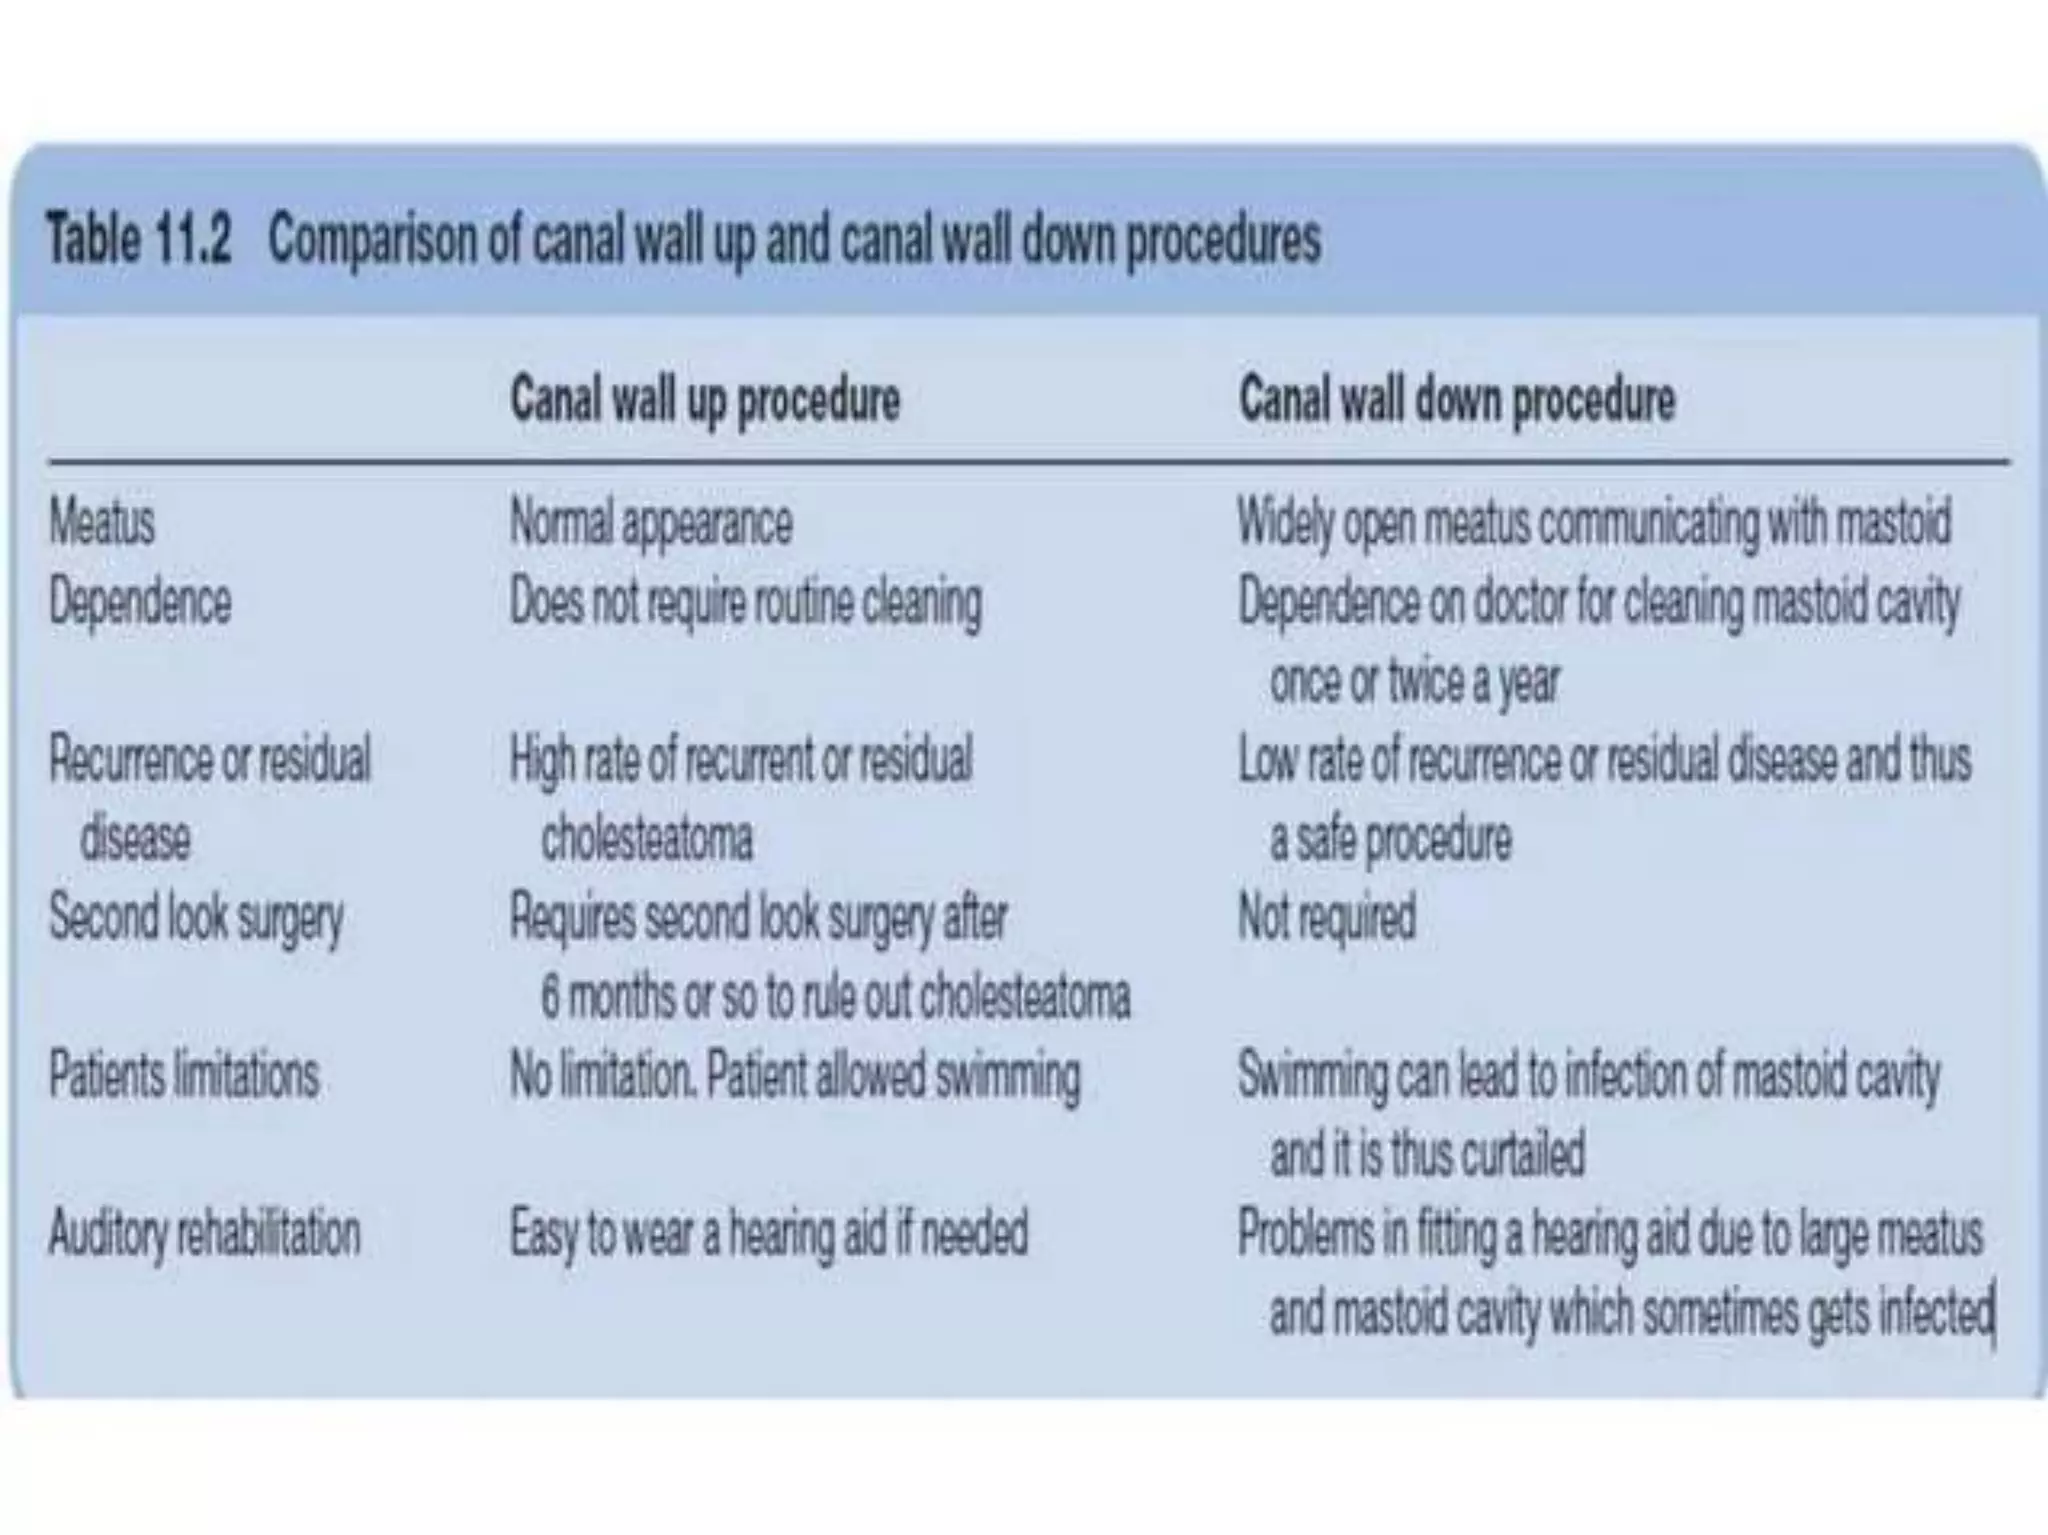

Chronic otitis media is a chronic inflammation of the middle ear and mastoid cavity that presents with recurrent ear discharge through a perforated eardrum. It has several subtypes depending on the state of the eardrum perforation and epithelium. It can be caused by prior acute otitis media, genetics, environment, eustachian tube issues, gastroesophageal reflux disease, craniofacial abnormalities, or immune deficiency.